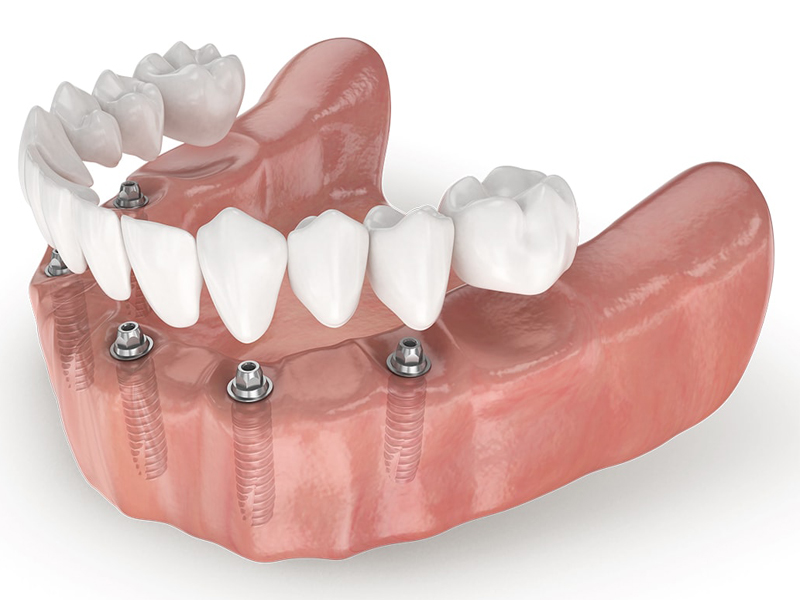

Implantology All on 6

The newAll on Six implant (All on 6) technique could be right for you if you already have a denture or a skeleton and you need to extract the last remaining teeth

• This solution is ideal if you want to have fixed teeth quickly, easily and without painful bone grafting;

• This technique can also be applied for those who are edentulous (toothless) for a long time;

• This operation is carried out after the panoramic and CT scan of the patient's dental arches;

• If there are certain conditions, the intervention can be performed with the transmucosal technique (at the discretion of the doctor).

Another great advantage that derives from the All on 6 method is the immediate load, on the inserted implants your new fixed teeth are fixed in the same session or at most in a second sitting after a few days.

Thanks to immediate loading, if there are certain conditions, it is no longer necessary to wait months before chewing on new teeth!